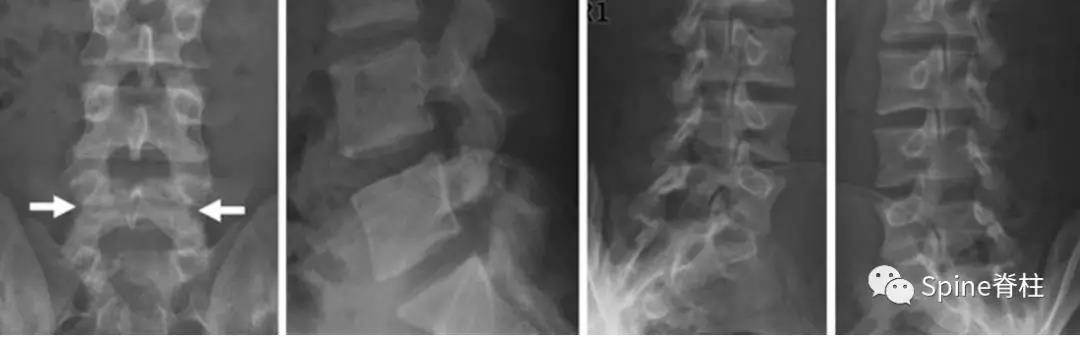

图:L4全椎板裂16岁男孩,3年严重腰痛,后伸受限其中L5椎体骶化